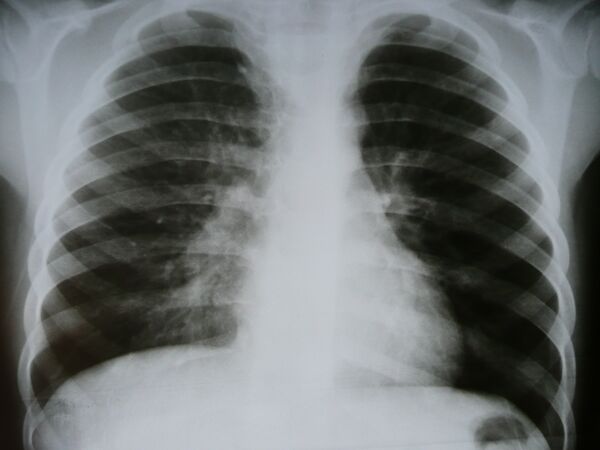

Инфильтра́т (от лат. in — в; filtratus — процеженный) — скопление в тканях организма клеточных элементов с примесью крови и лимфы. Наиболее часто встречаются воспалительный и опухолевый инфильтрат. Воспалительный инфильтрат состоит преимущественно из полиморфноядерных лейкоцитов (гнойный инфильтрат), эритроцитов (геморрагический инфильтрат), лимфоидных клеток (круглоклеточный инфильтрат), гистиоцитов и плазматических клеток (гистиоцитарно-плазмоклеточный инфильтрат) и др. Такие инфильтраты могут рассасываться, расплавляться, подвергаться склерозированию, с образованием каверны, абсцесса, рубца и т. п. Опухолевый инфильтрат состоит из опухолевых клеток различной природы (карцинома, саркома) и является проявлением инфильтрирующего роста опухоли. С образованием инфильтрата ткань увеличивается в объёме, меняет цвет, становится плотнее, иногда болезненна. В хирургической практике инфильтратом называется уплотнение, возникающее в тканях при их пропитывании анестезирующим (обезболивающим) раствором (см. Местная новокаиновая блокада).

Инфильтрат (infiltratus) — участок живой ткани, характеризующийся наличием обычно не свойственных ему клеточных элементов, увеличенным объемом и повышенной плотностью; иногда термин инфильтрат используется медиками для обозначения участка ткани, инфильтрированного каким-либо искусственно введённым веществом (напр., спиртом, антибиотиком, раствором анестезирующего средства).